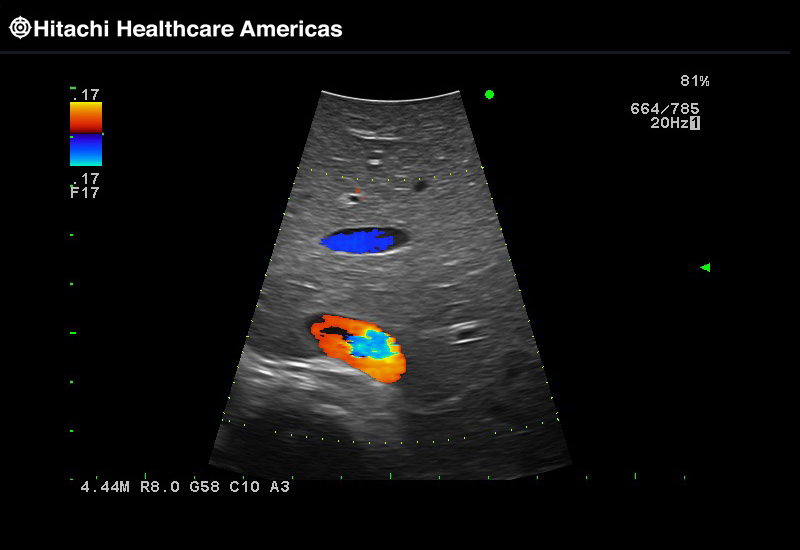

Superior guidance for all applications

Fujifilm Healthcare Americas is committed to designing tools that help surgeons navigate inside the human body and provide the necessary information to immediately make critical surgical decisions.

Fujifilm Healthcare's dedication to Surgeons provides outstanding ultrasound technology, professional support and the specialized tools necessary to best perform comprehensive real-time ultrasound imaging in Breast Surgery, General Surgery, Laparoscopic Surgery, Neurosurgery, Robotic Surgery and Surgical Oncology.

The Arietta 65 has many advanced and unique probes that fully cover the expanding range of procedures that benefit from ultrasound guidance.

The Arietta 65 has many advanced and unique probes that fully cover the expanding range of procedures that benefit from ultrasound guidance.